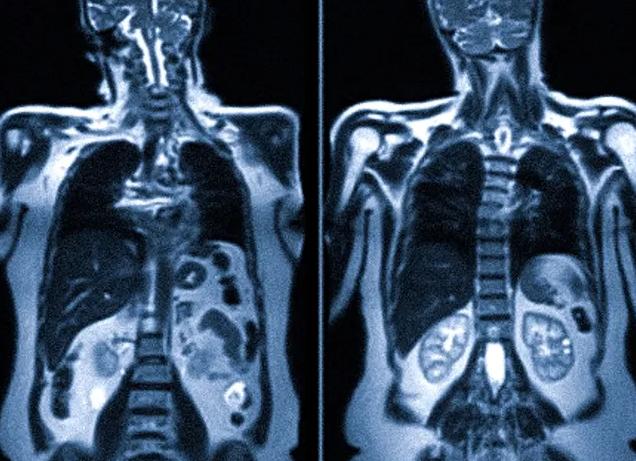

Магнитно-резонансная томография – это один из самых информативных способов исследования, при котором можно получить качественные снимки и компьютерные снимки внутренних органов. Электронный вид снимков позволяет детально рассмотреть все участки обследуемого органа, тканей. Аппарат выделяет минимальные дозы излучения, то при необходимости делать его можно довольно часто. Но, даже не смотря на данное утверждение, остается актуальным вопрос – МРТ-сканирование вредно ли для здоровья?

Качественные цифровые снимки после томографии позволяют оценить состояние органов (воспалительные процессы, опухоли).

Метод МРТ основывается на электромагнитных характеристиках атомов водорода, которые количественно преобладают над остальными частицами в тканях человека. Внутри томографа поддерживается постоянное магнитное поле высокой мощности, через него проходят радиосигналы с частотой близкой к частоте колебаний водорода. За счет резонанса происходит усиление радиоволны, что фиксируется в специальной матрице и преобразовывается компьютером в изображение.

Так как в различных тканях человеческого организма водород содержится в различном количестве, то исходящие сигналы от разных органов и тканей значительно отличаются, что позволяет получать достаточно точные изображения.